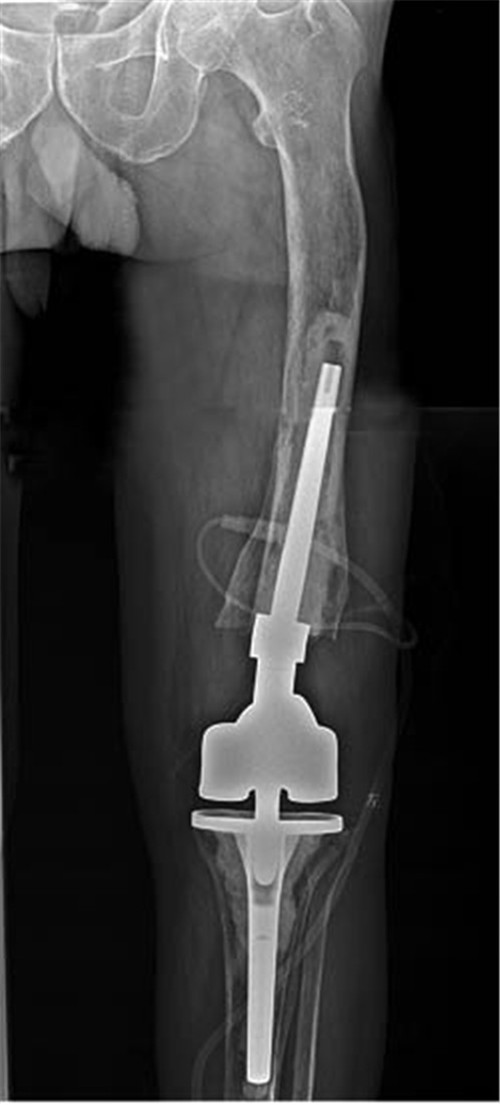

术后X线片

3D打印技术、计算机模拟技术、数字骨科和个体化设计是骨科未来发展的重点方向之一,这些技术在国际上处于起步阶段,在我国才处于临床摸索阶段。接受这些新的外科理念,可以使骨科手术向直观、可视化发展,符合精准医疗的理念。王坤正教授团队术前利用数字骨科技术三维重建,精确测量;获取数字化钢板及定制假体的数字模型,先后4次计算机模拟手术,最终确定出具有个体化特殊偏心柄的定制铰链膝及最佳手术方案;利用3D打印技术打印患膝关节实体模型,用定制膝关节假体在实体模型上,模拟手术;将实体模型手术模拟及计算机手术模拟中标定的截骨参数对比,结果准确无误。术前计划最终决定采取定制膝关节铰链膝假体,通过设计带有个体化偏心柄假体来达到股骨假体柄正确植入、矫正下肢力线的同时不做额外的关节内、外截骨矫形,股骨端垂直骨髓腔截骨,简化手术操作。术中根据模拟手术时的截骨参数进行膝关节置换,每步手术操作胸有成竹,甚至,通过术前实体模型模拟,可以预知术中两端长骨髓腔骨水泥的位置、厚度。取出的骨水泥与术前的模型骨水泥外形、体积几乎一致。手术截骨做到精确到厘米单位、缩短了手术时间、减轻了手术创伤,顺利完成了常规状态下,几乎无法完成的手术。